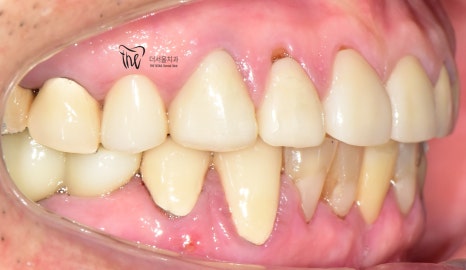

우선 교합면에서 바라보게 되면,

곳곳에 치아 결손 부위가 관찰이 되는데

이가 빠진지 시간이 꽤나 오래 되셨다는 것을

한 눈에 알아차릴 수 있습니다.

바로 결손부위를 보게 되면, 골 폭이 상당히

좁아져 있는 것을 볼 수 있는데 이는 치아 상실 후

방치 된 시간이 꽤나 오래 되었다는 것에 따른

반증이기 때문입니다.

정면에서 봤을 땐, 비심미적인 모습을 보여주며

곳곳에 치경부파절증의 증세들이 드러나고

있습니다. 따라서 ,식사를 하실 때 마다

지끈거리는 통증 및 이가 시린 느낌을 지속적으로

받아오셨다 말씀을 하셨었죠.